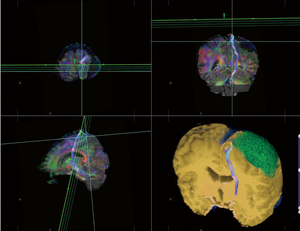

脳神経外科では、ziostation2の3D画像を、術前シミュレーションなど手術支援を中心に活用している。術前の3D画像作成を担当する吉岡史隆医長は、ziostation2について、「画像処理の速度が速く、ネットワークでフル機能が利用できるようになったので、外来や病棟で作業が可能になりました。作成した3D画像を使って、術前カンファレンスで低侵襲で機能温存が可能な術式やアプローチの方向などの検討を行っています。3D画像によって、血管と神経や脳の重要構造物との位置関係が容易に把握でき、手術の精度が向上しています」と説明する。

3D作成では、“CTサブトラクション”の精度が高いことを吉岡医長は評価する。「造影後のCTデータと差分することで、骨を抜いて血管だけを描出することが可能です。ziostation2では、骨に近い血管でも情報が欠けることなく、そのデータをもとに脳実質や腫瘍などとフュージョンすることで、より正確な3Dが作成できます」

また、MRIのDTI(Diffusion Tensor Imaging)データから神経線維を描出するトラクトグラフィーも、術前シミュレーションとして作成している。手術ナビゲーションシステムでもトラクトグラフィーの作成が可能で、術中はこちらのデータを使用するが、ziostation2のほうが精度が高いため、ziostation2の“MRトラクトグラフィー”を参照して、ナビシステムの画像を修正して使用しているという。

脳神経外科では術前シミュレーションに

ziostation2を活用

■ziostation2を用いた臨床画像

脳神経外科でのMRトラクトグラフィーによる |